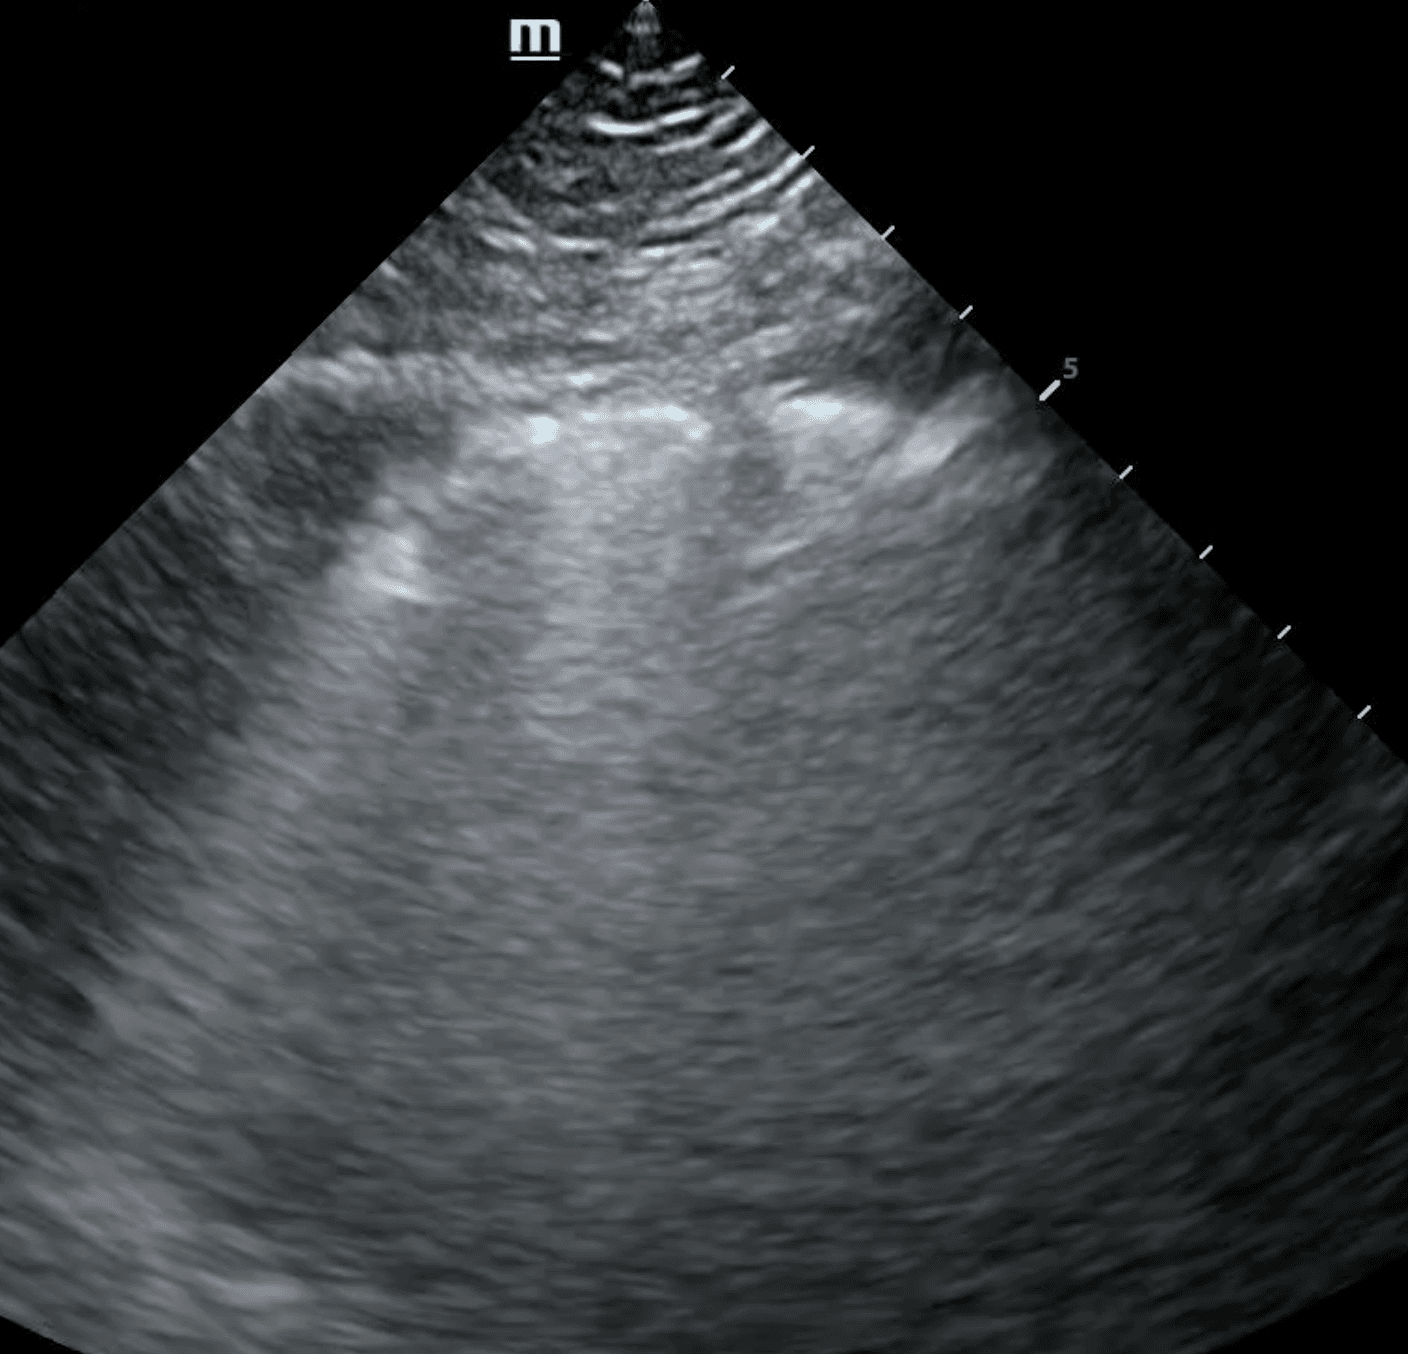

A subpleural consolidation refers to a consolidation underneath the pleural line. While all lung consolidations are technically subpleural, consolidations that extend through the entire lung are referred to as translobar. Compared to translobar consolidations, subpleural consolidations are smaller, tend to occur in the anterior lung and normal tissue can generally be viewed beneath the lesion. They tend to reflect an inflammatory cause, such as pneumonia, infarction from pulmonary embolism and metastatic lesions.

The shred sign, also known as a fractal sign, describes the border between abnormal and normal lung. It separates a subpleural consolidation from underlying normal lung. It has been described as “torn paper” as its irregular boundary contains jagged segments. Visualization of the shred sign helps localize focal consolidations that are likely to be missed on chest X-ray. This allows for early intervention to treat conditions such as pneumonia before they progress.